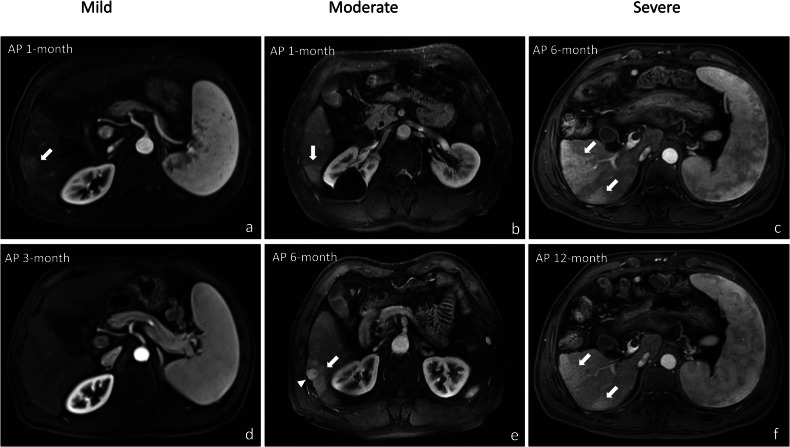

{"title":"Transient hepatic intensity differences: correlations with treatment outcomes and adverse events following DEB-TACE in hepatocellular carcinoma.","authors":"Noble Chibuike Opara, Shuwei Zhou, Weilang Wang, Shuhang Zhang, Xunjun Chen, Shenghong Ju, Yuan-Cheng Wang","doi":"10.1186/s13244-025-02041-2","DOIUrl":null,"url":null,"abstract":"<p><strong>Background: </strong>Transient hepatic intensity differences (THID) on MRI are commonly observed in hepatocellular carcinoma (HCC) patients following drug-eluting bead transarterial chemoembolization (DEB-TACE). We evaluated the association between THID, treatment outcomes, and adverse events in HCC patients treated with DEB-TACE.</p><p><strong>Materials and methods: </strong>This retrospective analysis included data from a prospective study conducted with 102 consecutive HCC patients treated with DEB-TACE between December 2017 and December 2020. The chi-square test assessed correlations between THID and adverse events, including biliary injury, intrahepatic metastasis, and portal venous thrombosis. Kaplan-Meier method evaluated overall survival (OS) and progression-free survival (PFS), with log-rank tests comparing THID complexity (simple vs complex) and severity (mild, moderate, and severe). Logistic regression identified factors associated with THID development.</p><p><strong>Results: </strong>Among the 102 HCC patients, 74 (72.5%) developed THID after DEB-TACE. Patients with THID had significantly higher rates of biliary injury (47% vs 14.3%, p = 0.002) and intrahepatic metastasis (25.7% vs 7.1%, p = 0.030). Complex THID was associated with worse PFS (p = 0.024). Moderate-to-severe THID had worse OS (p = 0.019) and PFS (p = 0.038). Factors associated with THID development included a higher tumor burden, baseline THID, and Child-Pugh class A.</p><p><strong>Conclusion: </strong>THID correlates with an increased risk of biliary injury and intrahepatic metastasis and is associated with worse OS and PFS in HCC patients following DEB-TACE.</p><p><strong>Critical relevance statement: </strong>THID development after DEB-TACE correlates with higher incidence of biliary injury, intrahepatic metastasis, and worse OS/PFS, emphasizing its potential as a critical imaging biomarker. This study advances clinical radiology by highlighting THID as an important factor in treatment outcomes.</p><p><strong>Key points: </strong>THID after drug-eluting bead transcatheter arterial chemoembolization correlates with treatment outcomes and adverse events in HCC. THID correlates with higher biliary injury, intrahepatic metastasis, and reduced survival rates. Complex or severe THID correlates with poorer survival in HCC patients.</p>","PeriodicalId":13639,"journal":{"name":"Insights into Imaging","volume":"16 1","pages":"164"},"PeriodicalIF":4.5000,"publicationDate":"2025-08-01","publicationTypes":"Journal Article","fieldsOfStudy":null,"isOpenAccess":false,"openAccessPdf":"https://www.ncbi.nlm.nih.gov/pmc/articles/PMC12316659/pdf/","citationCount":"0","resultStr":null,"platform":"Semanticscholar","paperid":null,"PeriodicalName":"Insights into Imaging","FirstCategoryId":"3","ListUrlMain":"https://doi.org/10.1186/s13244-025-02041-2","RegionNum":2,"RegionCategory":"医学","ArticlePicture":[],"TitleCN":null,"AbstractTextCN":null,"PMCID":null,"EPubDate":"","PubModel":"","JCR":"Q1","JCRName":"RADIOLOGY, NUCLEAR MEDICINE & MEDICAL IMAGING","Score":null,"Total":0}

Results: Among the 102 HCC patients, 74 (72.5%) developed THID after DEB-TACE. Patients with THID had significantly higher rates of biliary injury (47% vs 14.3%, p = 0.002) and intrahepatic metastasis (25.7% vs 7.1%, p = 0.030). Complex THID was associated with worse PFS (p = 0.024). Moderate-to-severe THID had worse OS (p = 0.019) and PFS (p = 0.038). Factors associated with THID development included a higher tumor burden, baseline THID, and Child-Pugh class A.